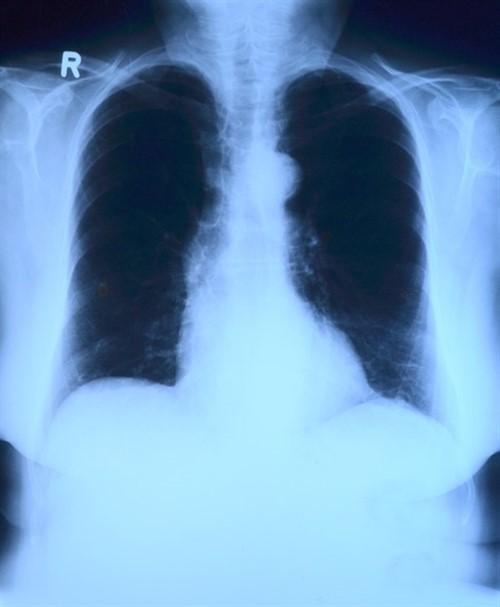

La inteligencia artificial mejora la capacidad de los médicos para diagnosticar enfermedades pulmonares

La inteligencia artificial (IA) puede ser una ayuda inestimable para ayudar a los médicos de pulmón a interpretar los síntomas respiratorios con precisión y hacer un diagnóstico correcto, según una nueva investigación que se presenta este miércoles en el Congreso Internacional de la Sociedad Respiratoria Europea, que se celebra en París, Francia.